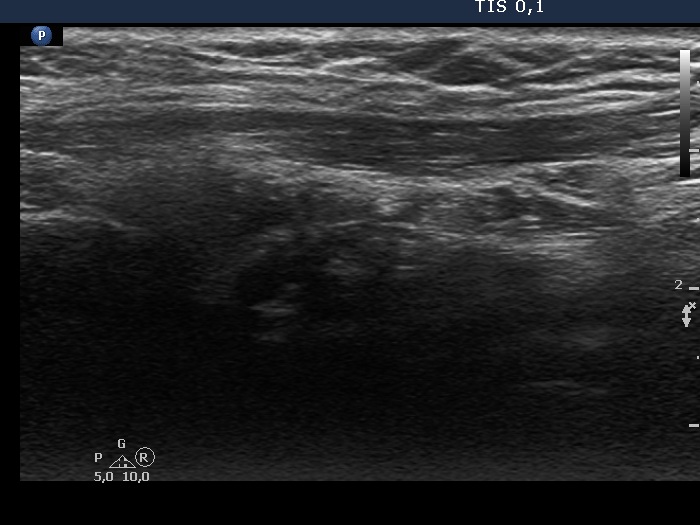

The operated thyroid - case 337 (ultrasonographic picture 7)

Left lobe, another longitudinal scan. The hypoechoic mass has upper and lower tails which means that this does not correspond to thyroid tissue but to muscle fiber.